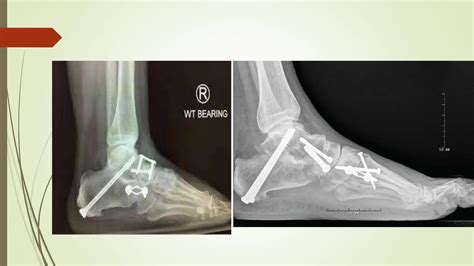

• Fixation: The bones are aligned and held in place using screws, plates, or rods. These fixation devices provide stability while the bones heal and fuse together.

• Non-Weight-Bearing Period: For the first few weeks, you will need to keep weight off your ankle to allow the bones to heal properly. This may involve using crutches, a walker, or a wheelchair.